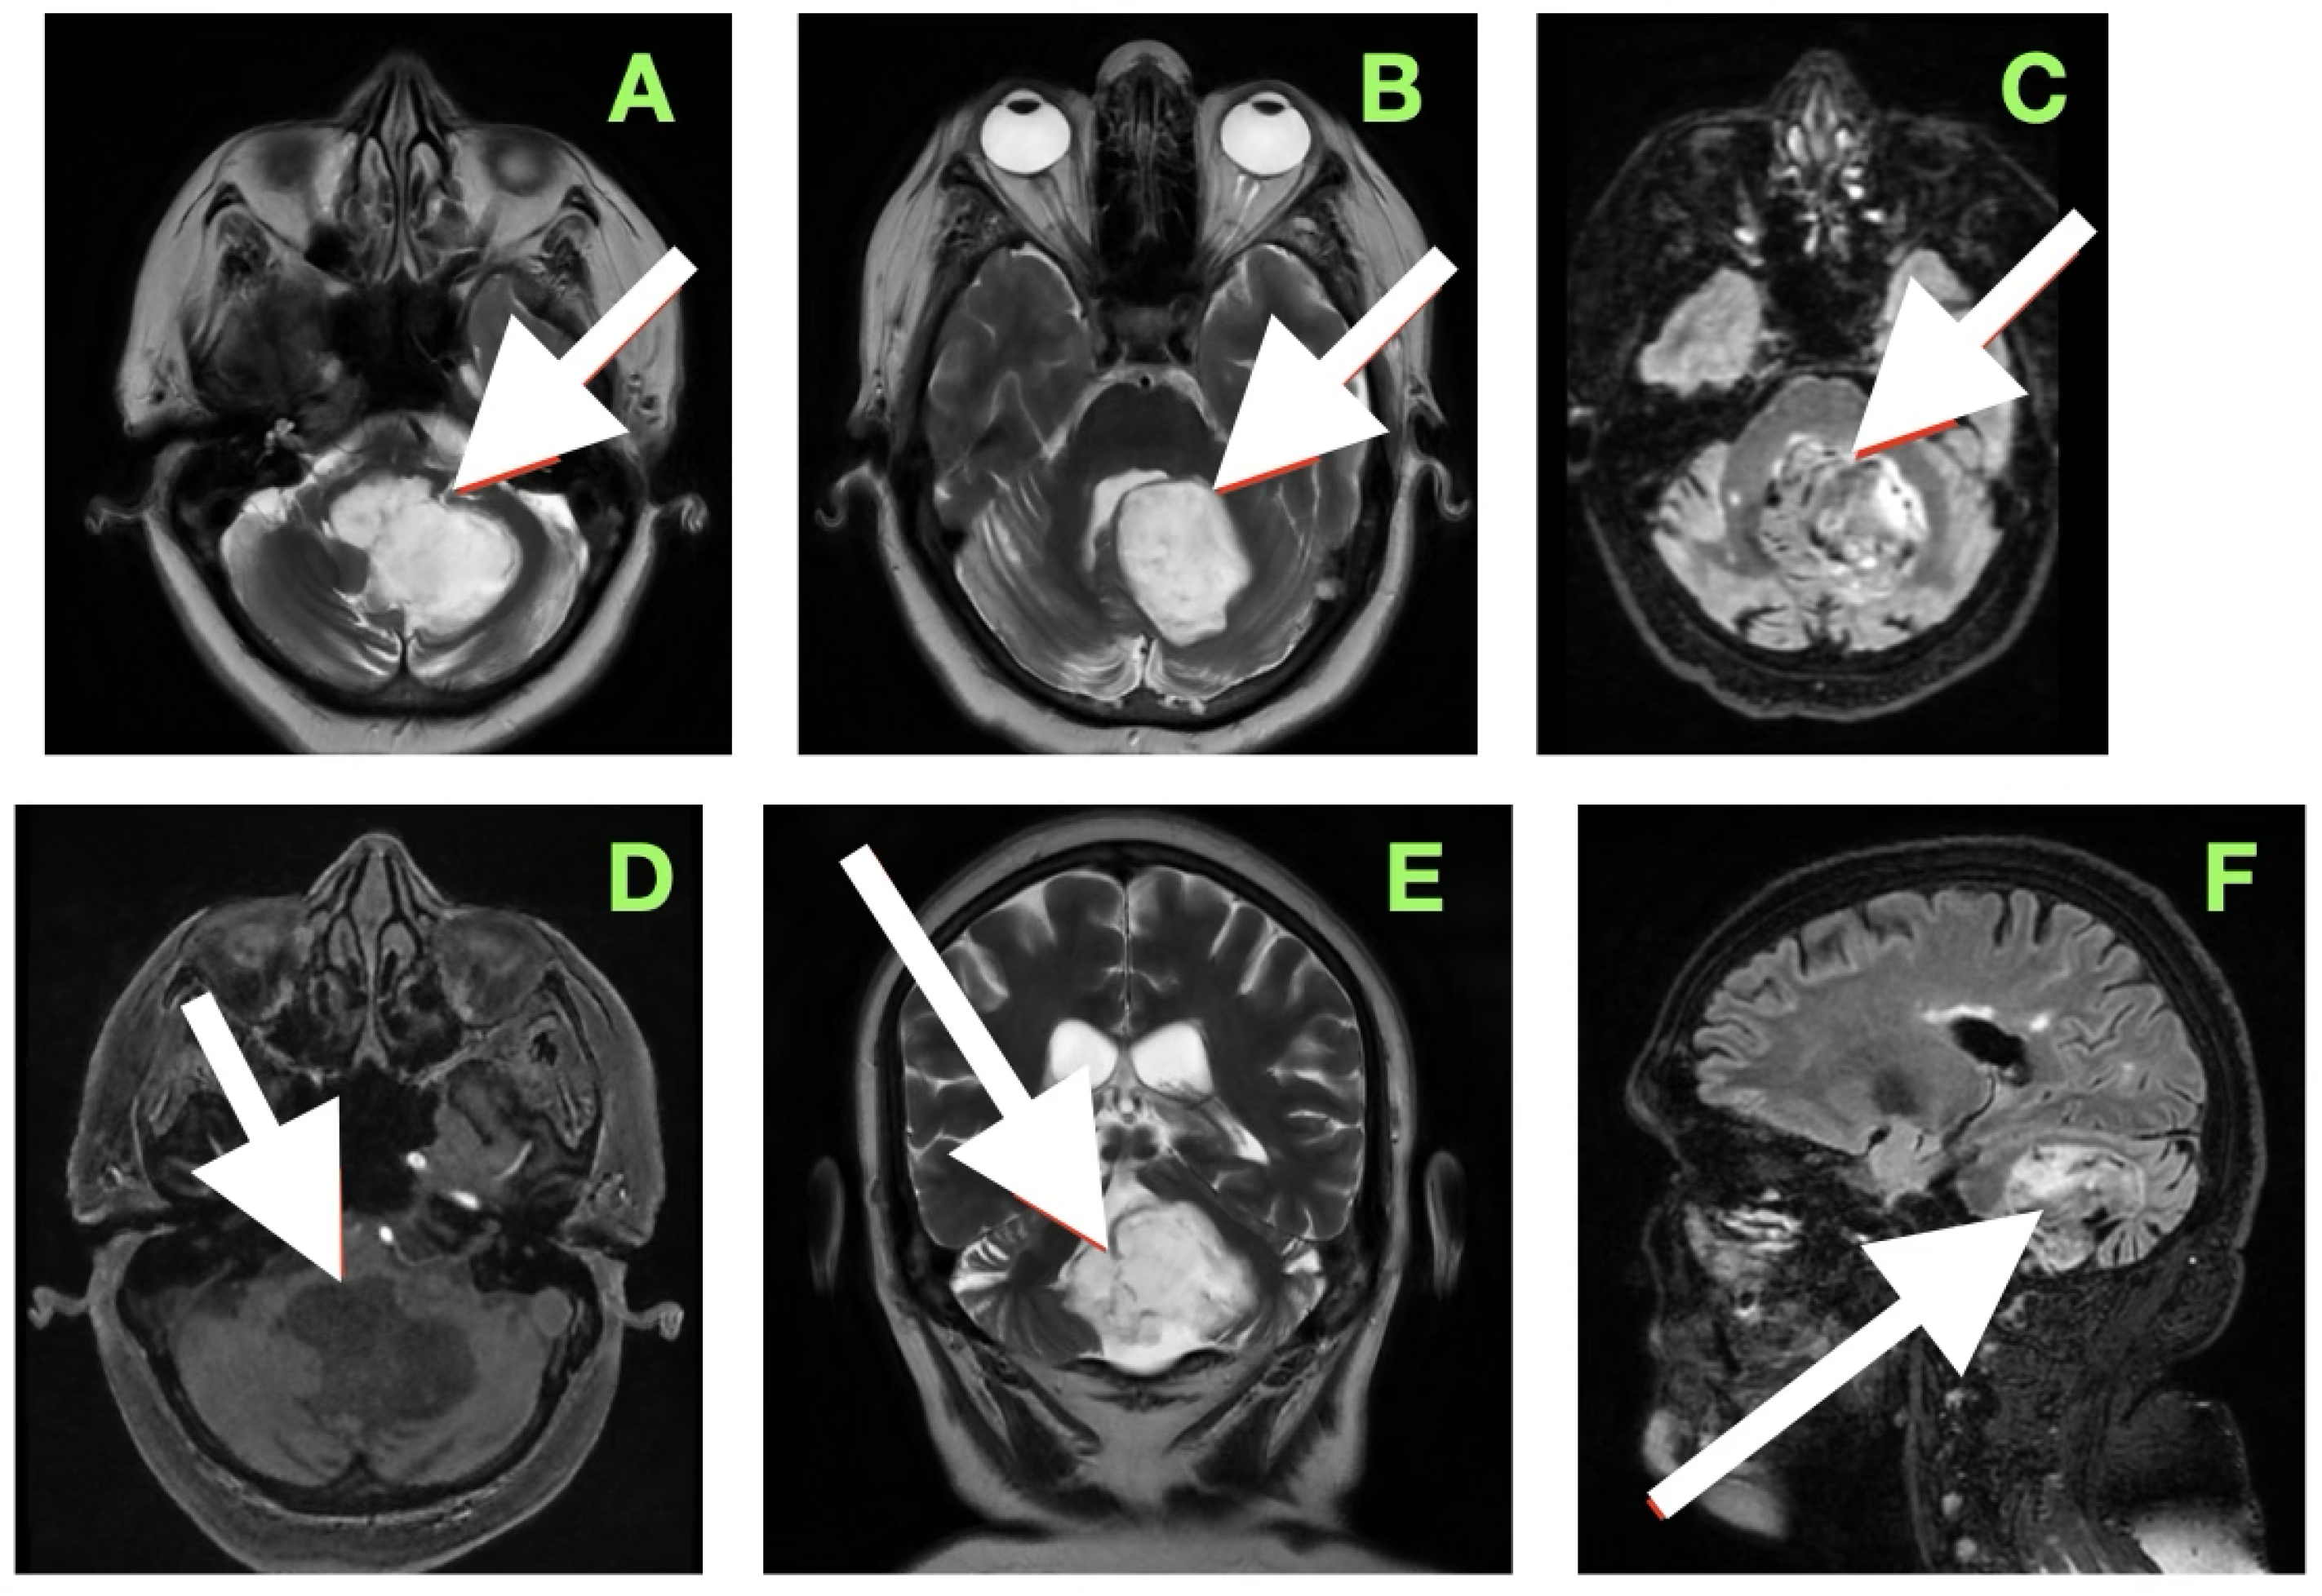

High-resolution MRI with selective MRA was obtained immediately after the examination to determine the spatial extent of the mass, vascular relationships to it, and to evaluate the current status of cerebrospinal fluid dynamics. Sagittal MRA reconstruction (Figure 1) revealed a large extra-axial mass in the left posterior fossa that centered on the cerebellar hemisphere and extended medially into the vermis. Posterior fossa arteries were lengthened and changed their course: the posterior inferior cerebellar artery (PICA) appeared to follow an elongated superior–posterior course along the dorsal surface of the mass with maintained continuity and caliber, the anterior inferior cerebellar artery (AICA), and small cerebellar perforators were also pushed to the left but appeared to be unaffected. The gradual vascular displacement without distortion, alteration, or irregularity would be consistent with chronic adaptive remodeling of the vessels; acute distortion did not occur, and there was no vascular blush, arteriovenous shunt, and/or feeding-vessel hypertrophy, identifying the extra-axial mass as an avascular, space-occupying lesion consistent with an epidermoid tumor.

Axial T2-weighted sequences (Figure 2A,B) revealed a large, lobulated mass occupying most of the left cerebellar hemisphere, insinuating between folia and extending across the midline into the inferior vermis. The lesion was markedly hyperintense compared to cerebellar parenchyma, with internal heterogeneity suggesting layered keratinaceous content. The inferior pole of the mass descended into the cisterna magna, and its medial aspect encroached on the fourth ventricle, partially effacing it and displacing its floor anteriorly over the dorsal medulla. This displacement explained the patient’s severe truncal instability, as vermian compression interrupts integration of proprioceptive and vestibular input, and also her left-sided appendicular ataxia, arising from disruption of cerebellar hemispheric coordination pathways projecting through the dentate nucleus and superior cerebellar peduncle.

Susceptibility-weighted imaging (Figure 2C) showed tiny punctate hypointense lesions foci within lesions, suggestive of microcalcifications or hemosiderin secondary to chronic contact with the tentorium, vasculature, and pia, all indicating a long-standing, slowly growing mass. Post-contrast T1-weighted imaging (Figure 2D) displayed no enhancement, considering both lesions were different from a meningioma, hemangioblastoma, or metastasis. Coronal T2-weighted sequences (Figure 2E) demonstrated inferior and lateral extension to the foramina of Luschka, stenosing the lateral recesses of the fourth ventricle and displacing the cerebellar peduncles, most notably left. This accounted for the gaze-evoked nystagmus and pursuit deficits, considering vestibulocerebellar input and flocculonodular output. Cerebellomedullary junctional contact was responsible for the subtle bulbar discoordination secondary to pressure to the dorsal medulla near the nucleus ambiguus. Sagittal FLAIR (Figure 2F) showed an anteriorly displaced brainstem; however, the dorsal medulla was compressed against the wall of the fourth ventricle, with the pontomedullary junction displaced anteriorly. The prepontine cistern was partly effaced, and the basal cisterns were narrowed but still patent; however, inferior edema was enough for acute obstructive hydrocephalus.

Overall, the clinical–imaging cumulative data provided support for the diagnosis of an extra-axial, slow-growing epidermoid cyst, with lobulated margins, displacing the subarachnoid space, non-enhancing, and displacing chronic vessels. The MRI-clinical correlation was telling—compression via the vermis for truncal ataxia, hemispheres for dysmetria and dysdiadochokinesia, peduncles for pursuing instability, and medulla for bulbar signs. Severe compression of the fourth ventricle and effacement of the cisterns defined surgical urgency and targets that day.

Figure 2. Preoperative magnetic resonance imaging of the posterior fossa. (A,B) Axial T2-weighted images reveal a large lobulated hyperintense lesion occupying the left cerebellar hemisphere, extending medially into the vermis and inferiorly into the cisterna magna, with partial effacement and anterior displacement of the fourth ventricle. The lesion insinuates between cerebellar folia without a discrete capsule, a feature characteristic of epidermoid tumors. (C) Susceptibility-weighted imaging shows punctate hypointense foci within the lesion, likely representing calcific or hemosiderin deposits from chronic contact with adjacent neurovascular structures. (D) Axial post-contrast T1-weighted image demonstrates absence of enhancement, distinguishing the lesion from hypervascular posterior fossa neoplasms. (E) Coronal T2-weighted image depicts inferior extension toward the foramen of Luschka and compression of the cerebellar peduncles, explaining the patient’s gait instability, gaze-evoked nystagmus, and dysdiadochokinesia. (F) Sagittal FLAIR sequence confirms anterior displacement and flattening of the dorsal medulla with partial effacement of the prepontine cistern, correlating with the subtle bulbar incoordination observed on examination.